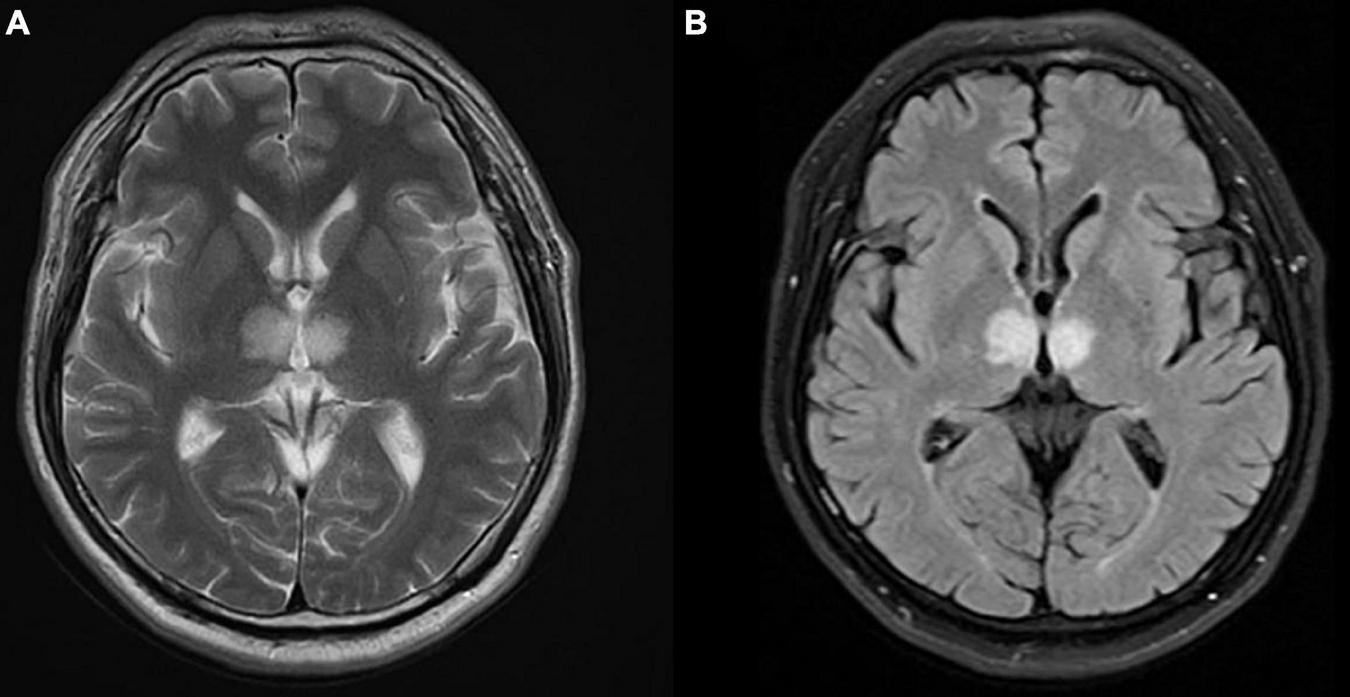

In the cardiac care unit, the patient’s consciousness gradually improved but still presented moderate drowsiness. To ascertain the pathogenesis of altered consciousness, a head MRI was ordered on the third day after the procedure. It showed symmetrical lesions in the paramedian thalamus, in the territory of the artery of Percheron. The lesions presented with an abnormal restriction of water diffusion on diffusion-weighted imaging (DWI) and hyperintensity in FLAIR and T2-weighted sequence on the paramedian thalamus level, without the midbrain involved (Figures 2, 3). MRI and corresponding clinic manifestations confirmed the diagnosis of an AOP infarction.

FIGURE 3

Axial magnetic resonance imaging (MRI) presenting bilateral high-signal intensity on the paramedian thalamus in (A) T2-weighted sequence, and (B) FLAIR sequence.